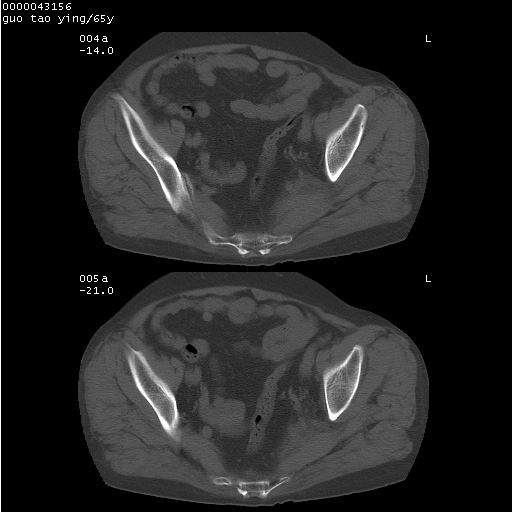

以下是引用黑白光影在2008-1-30 13:22:00的发言:[br]支持左耻骨骨折。[br]未见骶骨骨质明确破坏改变。[br]经楼主提示(勿局限于外伤)。考虑为右侧腹股沟直疝。[br][br][br][br]